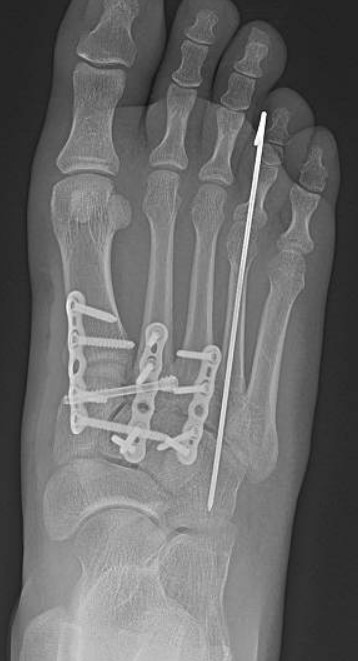

Led by Dr. Vinod Panchbhavi, a world-renowned orthopaedic foot and ankle surgeon, our fellowship covers all aspects of foot and ankle surgery including trauma, reconstruction, ligament and tendon injuries, arthroscopy, arthroplasty, and midfoot and

education. While he practices all aspects of foot and ankle surgery, he has made especially significant contributions in advancing our understanding of charcot arthropathy and Lisfranc injuries.

- Clinical exposure: Between the three attendings, you will have between 500-800 cases for the year, covering all aspects of foot and ankle surgery. Each attending has his own operating style and have different backgrounds so you will be exposed to

a variety of techniques and methods. In addition, UTMB provides medical care to the Texas Department of Criminal Justice, which allows for exposure to some of the most complex pathology possible. Finally, the fellowship is very hands-on and graduated

autonomy is given early and often.